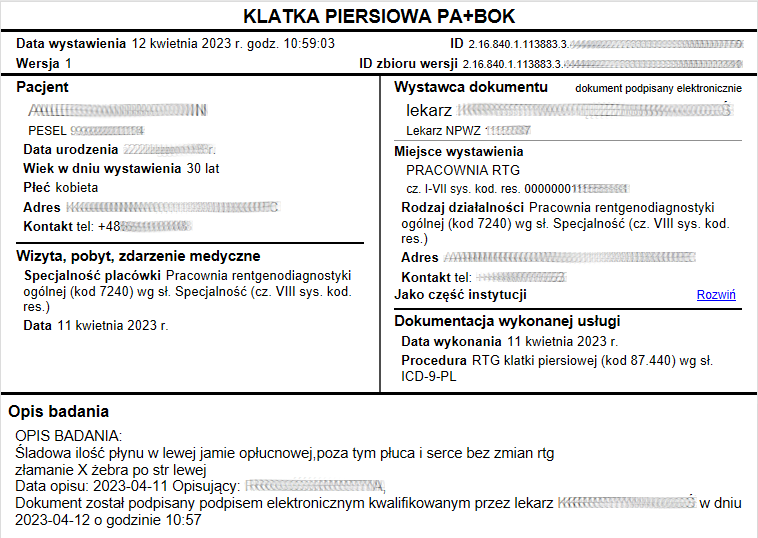

Raportowanie zdarzeń medycznych i udostępnianie EDM do systemu P1

Rozwiązanie zawiera wszystkie elementy informatyczne umożliwiające obieg informacji medycznej, pozwala na tworzenie i udostępnianie elektronicznej dokumentacji medycznej EDM. Integracja pomiędzy systemem medycznym i systemem PACS umożliwia przekazywanie zleceń na badania i odbieranie wyników oraz rozliczenia usług. Opcjonalnie system umożliwia wysyłanie badań do zdalnego opisu.

Oferujemy dla naszych Klientów dostawę i uruchomienie rozwiązania informatycznego, które umożliwia obieg informacji medycznej pomiędzy gabinetem lekarskim i pracownią diagnostyki obrazowej. W efekcie nie tylko usprawnia się proces leczenia pacjenta, ale również rozliczenie usług diagnostyki obrazowej. Dodatkowo system umożliwia raportowanie zdarzeń medycznych z diagnostyki obrazowej do systemu P1.